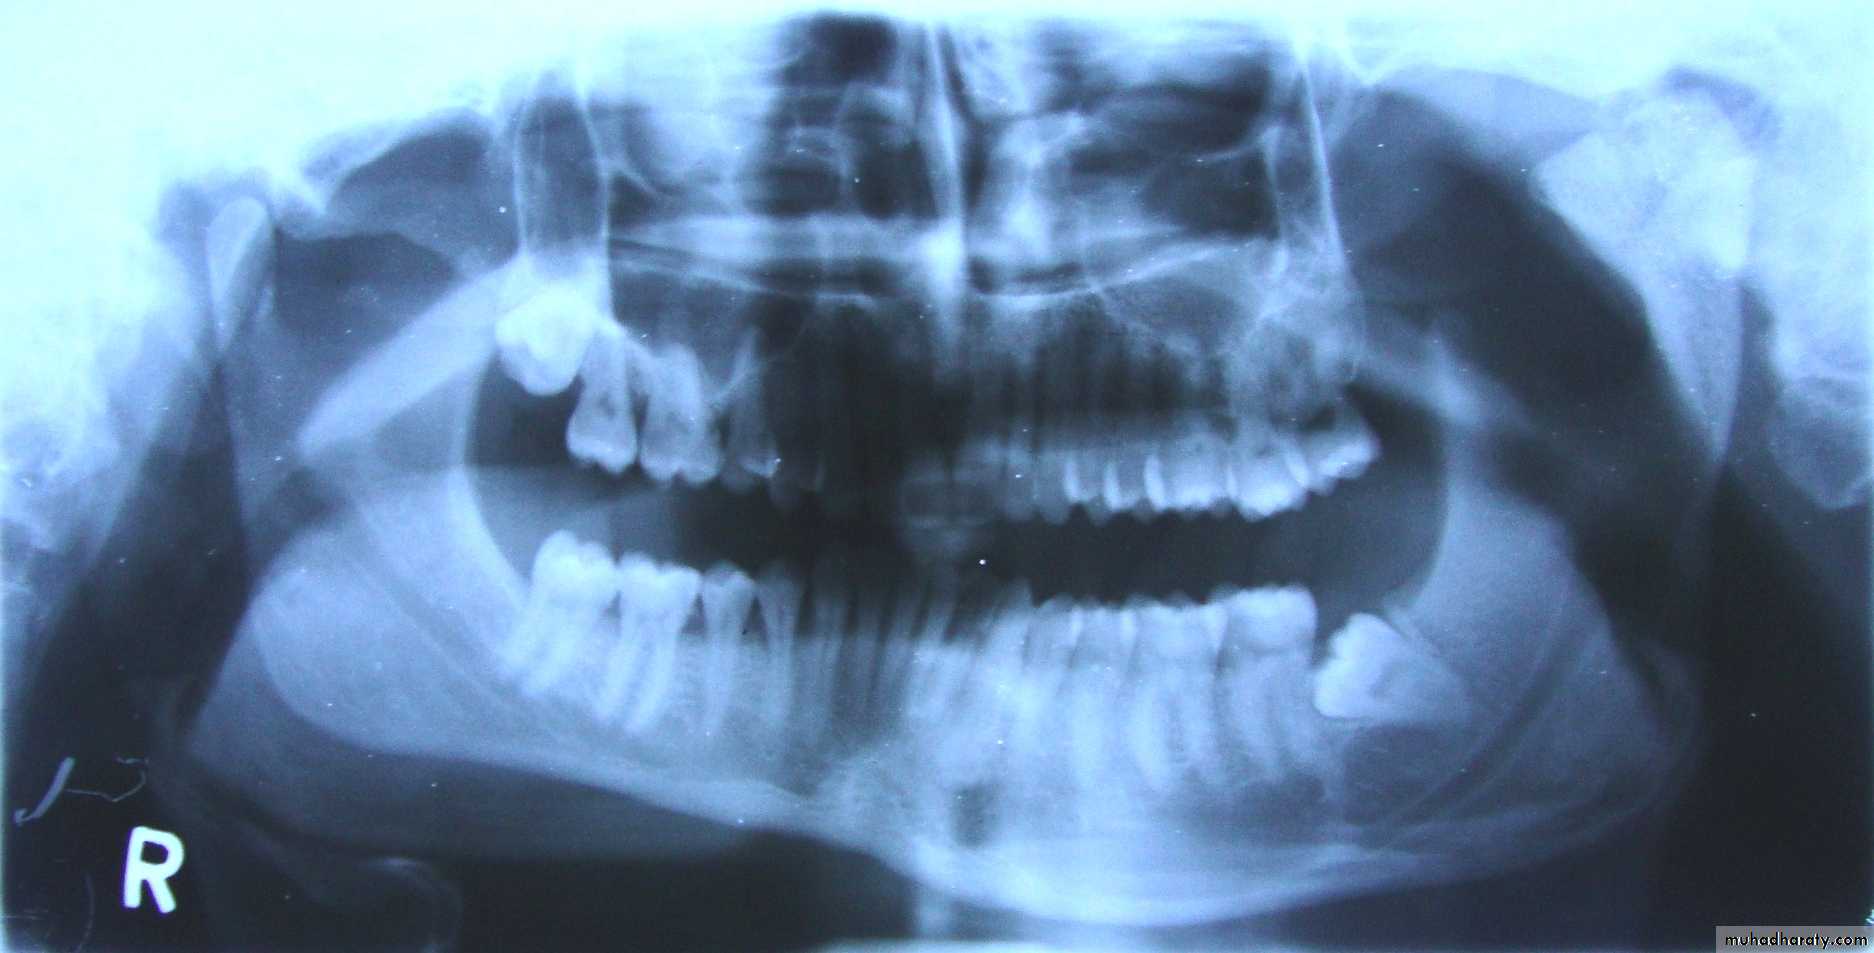

Condyle Hyperplasia

It is a unilateral or bilateral increase in the condyle growth due to local or systemic causes.Features

• Limited mouth opening with occasion pain

in the TMJ.

• Deviation of mandible to the unaffected side with facial asymmetry.

• Open bite on affected side with maxillary cant

• Treated by orthognathic surgery, without any permanent facial deformities, if done at an early age.

• Condylectomy or condyloplasty may also be done in some mild cases.

24Condyle Hyperplasia

26Condyle Hyperplasia

27Condyle Hyperplasia